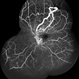

- FFA in a case of Racemose angioma

- 42 year old male, presented with blurred vision . Examination revealed Racemose angioma. FFA was done which revealed tortuosity of blood vessels.